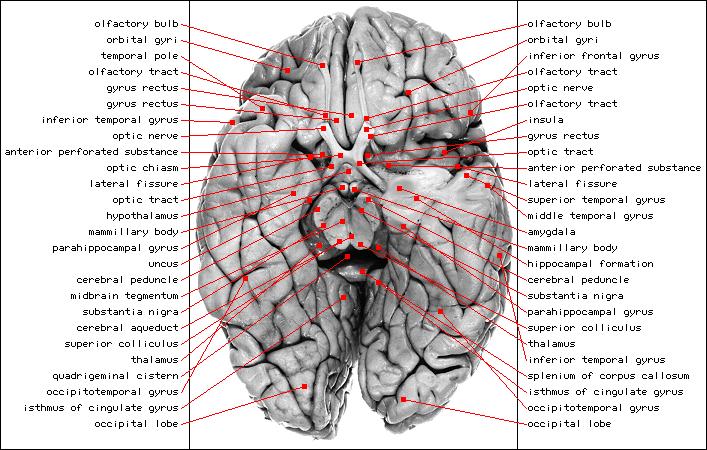

This page serves as an introduction to Functional Neuroimaging

I will mainly focus on a single imaging technique:

functional Magnectic Resonance Imaging

Desktop brain surgery

The resources listed below will enable you to explore free

data from real experiments on living brains using free

Neuroimaging software running on several operating systems